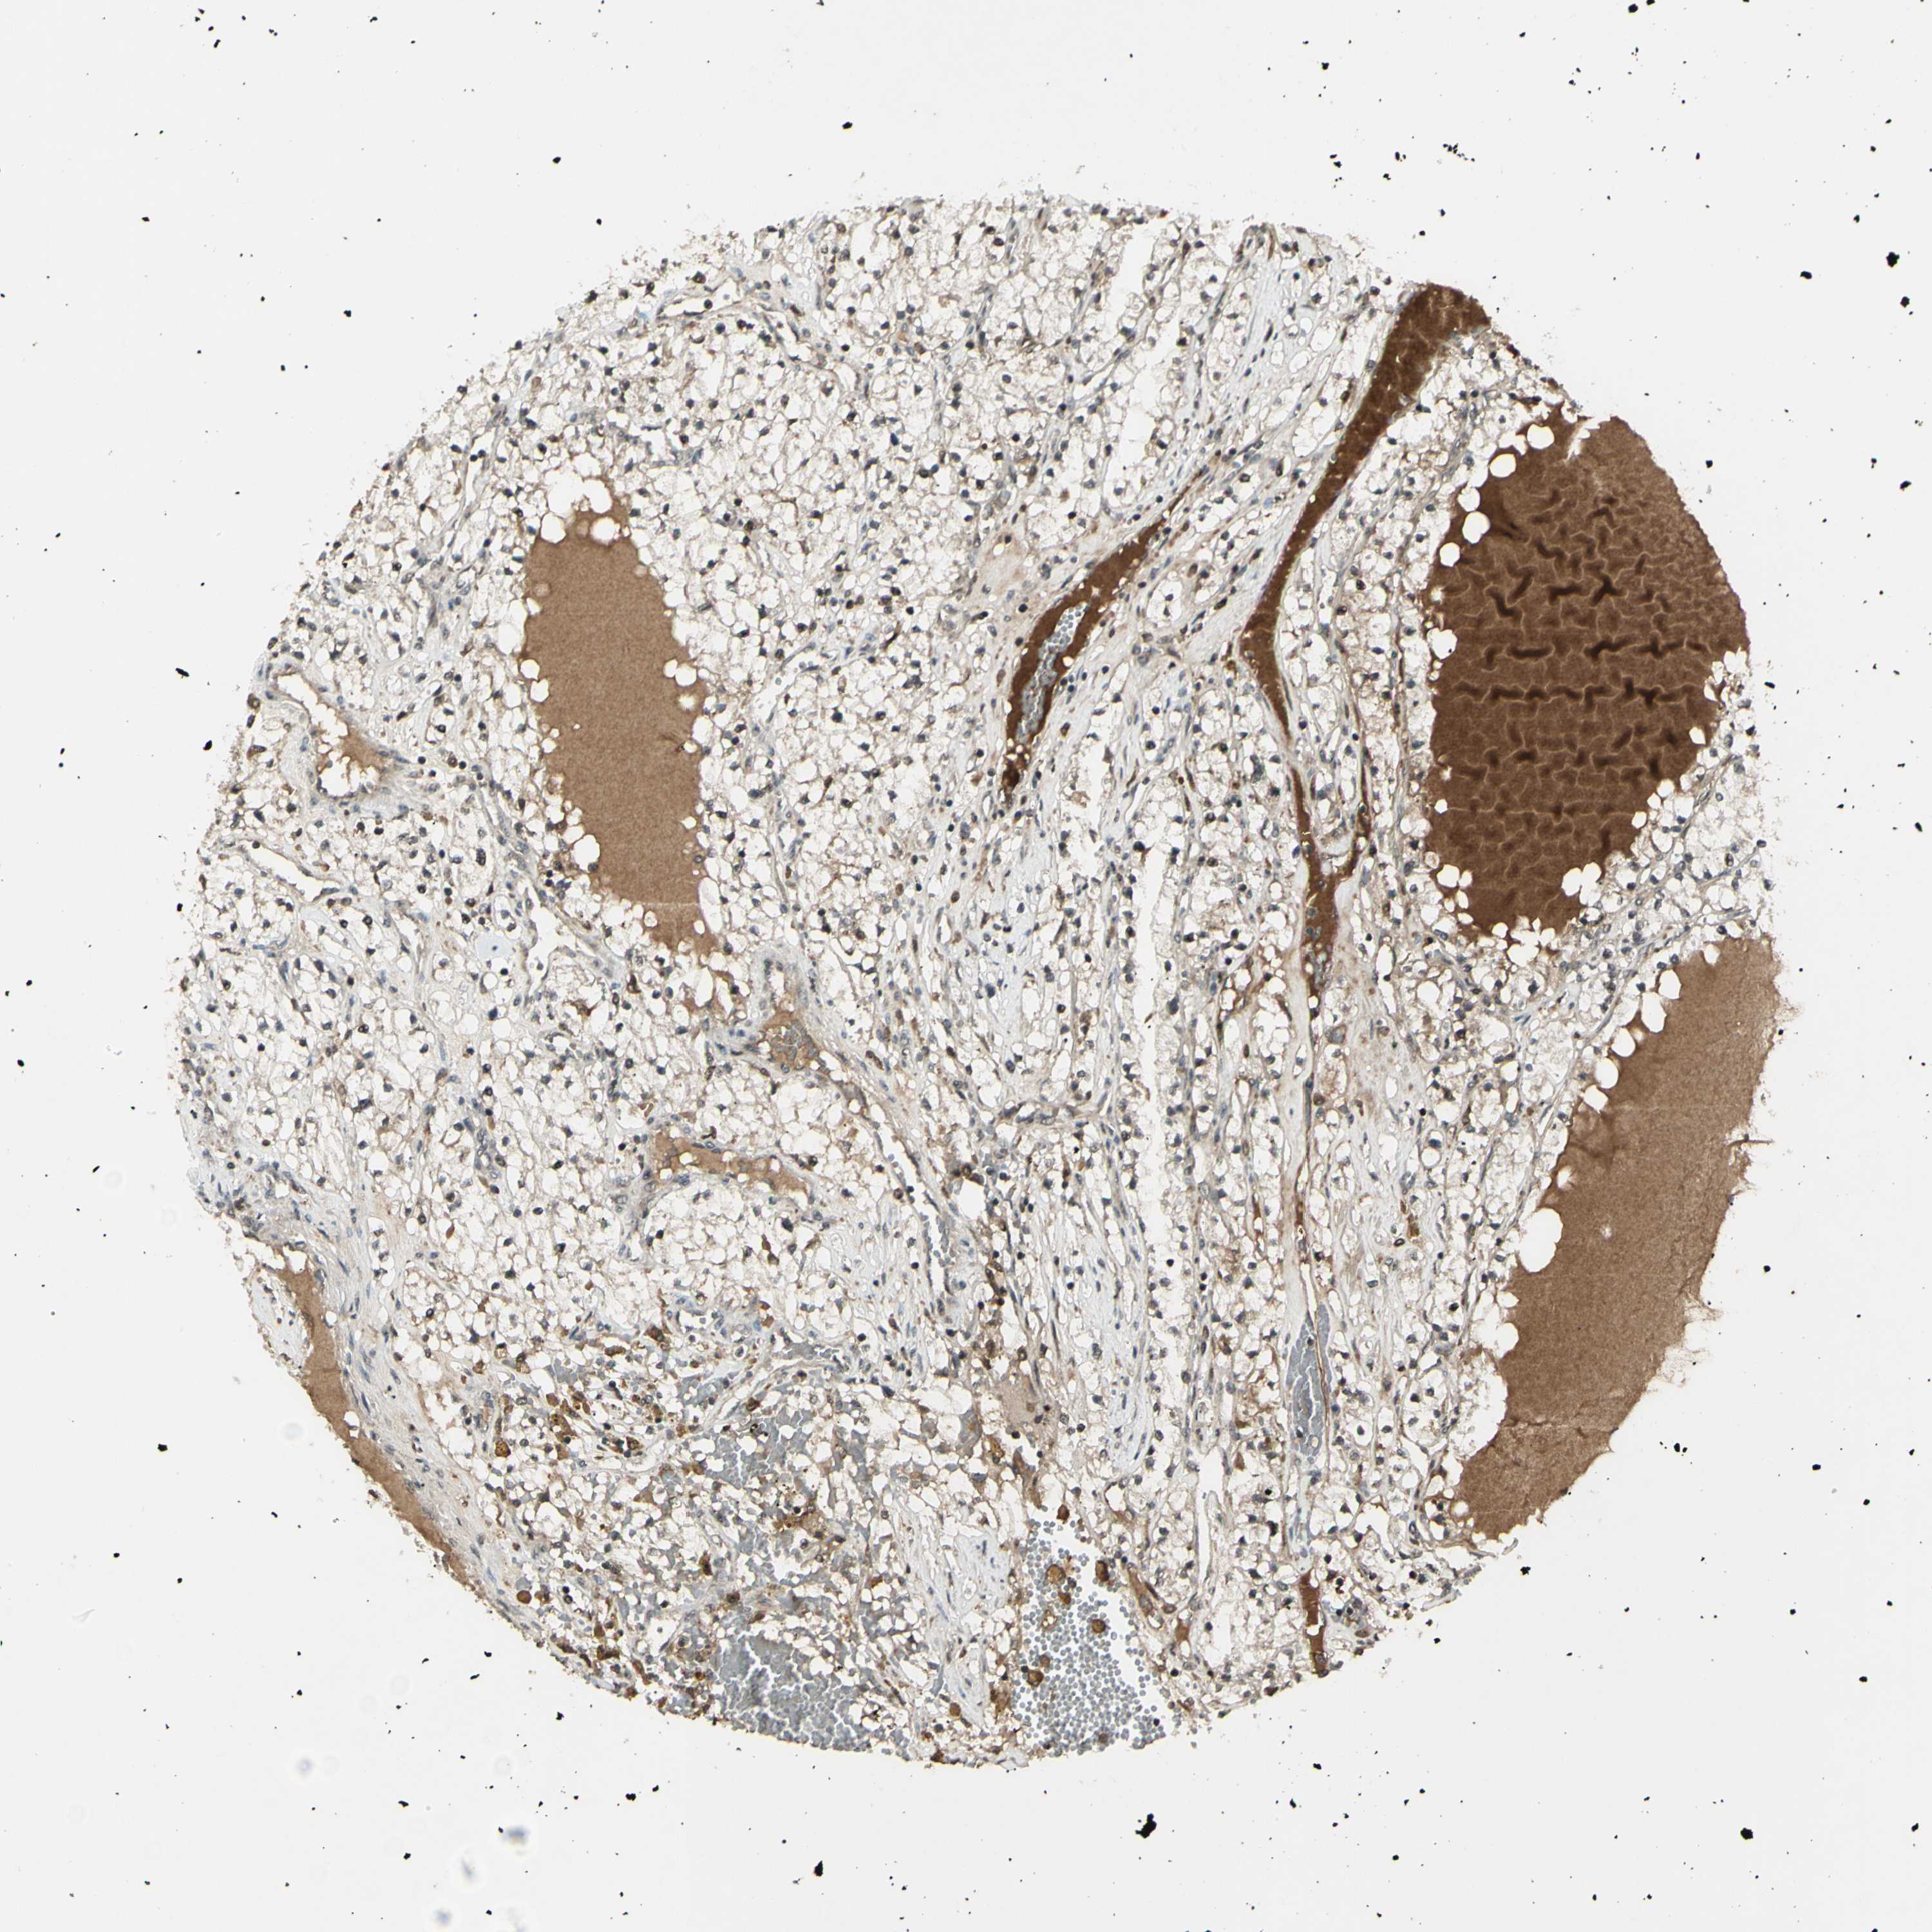

CANCER RENAL CANCER Show tissue menu

KICH TCGA KIRC TCGA KIRC VALIDATION KIRP TCGA PROTEIN RCC CPTAC PROTEIN EXPRESSION